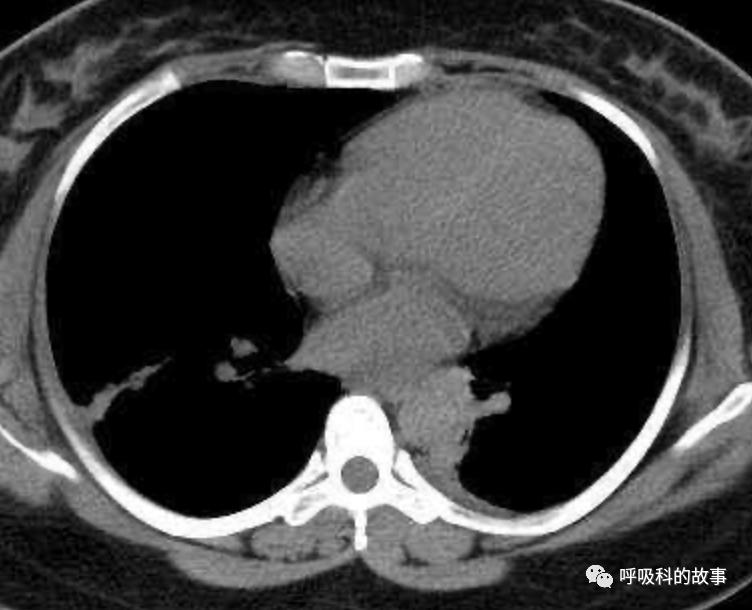

上面三张图分别是第一、二、三周的体温单